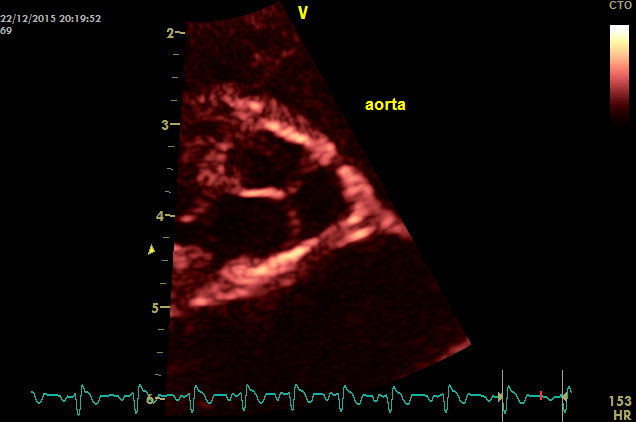

come si puo’ notare dai particolari nelle immagini zoom la struttura valvolare appare integra con una normale conformazione delle cuspidi la turbolenza e’ generata da una piccola banda fibrosa sottovalvolare ,in questo caso a dispetto delle alterazioni minime visualizzabili nell’esame B mode la stenosi sulla base del gradiente appare severa ,il PHT inferiore ai 300mm/sec dell’insufficienza aortica che quasi sempre accompagna la stenosi indica pressioni diastoliche nel ventricolo sx elevate